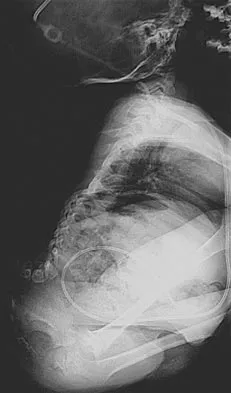

A 44-year-old woman has had lower extremity dysesthesias, urinary incontinence, and has been unable to walk for the past 2 days. She reports no pain or history of trauma. She notes that 3 weeks ago she missed work for 2 days because of back pain, but it resolved with rest. Examination shows decreased or absent sensation below the knees, no motor function below the knees, and decreased rectal tone. Catheterization results in a postvoid residual of 2,000 mL. Plain radiographs and MRI scans without contrast are shown in Figures 1a through 1d. What is the next most appropriate step in management?

Explanation

The patient has had a clear and sudden onset of a profound neurologic deficit. The radiographic studies suggest a lesion in the conus medullaris that appears to be intradural and intramedullary. MRI, with and without contrast, will best evaluate this mass further. The addition of gadolinium allows further evaluation of vascularity and the extent of the lesion. Eichler ME, Dacey RG: Intramedullary spinal cord tumors, in Bridwell KH, Dewald RL (eds): The Textbook of Spine Surgery, ed 2. Philadelphia, PA, Lippincott-Raven, 1997, vol 2, pp 2089-2116.